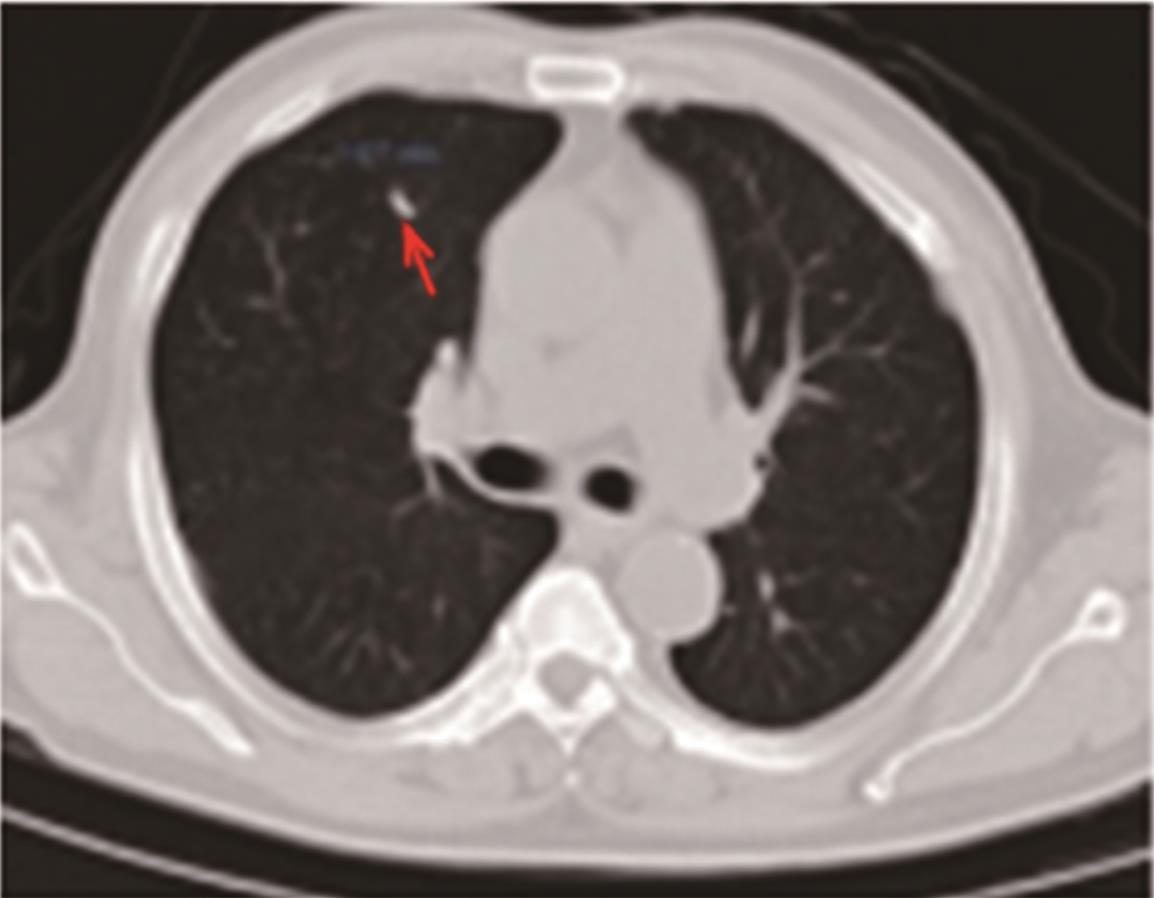

• 转移性上尿路上皮癌在维迪西妥单抗联合替雷利珠单抗新辅助治疗后行根治性肾盂癌切除术1例报道

2023, 48(8):1005-1008. DOI: 10.13406/j.cnki.cyxb.003299

摘要 (52) HTML (36) PDF 2.16 M (1929) 评论 (0) 收藏

摘要: